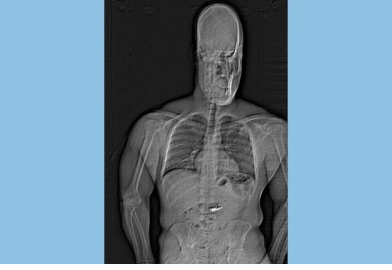

Ảnh chụp x-quang cho thấy "vật thể lạ" trong nội tạng của Jaythan Gilder. Ảnh: Cảnh sát Orlando.

Khi bị bắt giữ, Gilder đã lập tức nuốt nhiều vật thể nghi là hai đôi bông tai kim cương bị đánh cắp. Báo cáo của cảnh sát ghi nhận, tại trại giam hạt Washington, kết quả chụp X-quang cho thấy có "vật thể lạ" trong dạ dày của người đàn ông này.

"Những vật thể này được nghi là trang sức từ vụ trộm và sẽ cần thu hồi sau khi chúng qua hệ tiêu hóa của Gilder", điều tra viên Aaron Goss viết trong bản báo cáo.